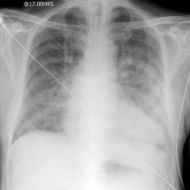

APO.jpg

وذمة رئوية حادة

تظهر العلامات الشعاعية عادة قبل ظهور العلامات السريرية وأولى هذه العلامات هي تشوش الحدود الواضحة للأوعية الرئوية الرئيسية في السرتين مع تغيم منتشر في الرئتين (منظر الغشاء المغشى).

وكلما تطورت الوذمة ظهرت كثافات عقدية إضافة إلى علامات تكثف سنخي وازدادت الكثافة في السرتين وتدعى علامة جناحي الخفاش Wing Bat’s وهي علامة مميزة.

ومن العلامات الشعاعية المرافقة وجود دليل على إصابة قلبية بدئية كضخامة البطين الأيسر، كما أن زيادة الضغط في الأذينة اليسرى وزيادة الضغط الخلالي قد يسببان نقصاً في ضخ الأوعية الرئوية إلى الأقسام السفلية من الرئتين وبالتالي إلى تحول الجريان إلى الأقسام العلوية.